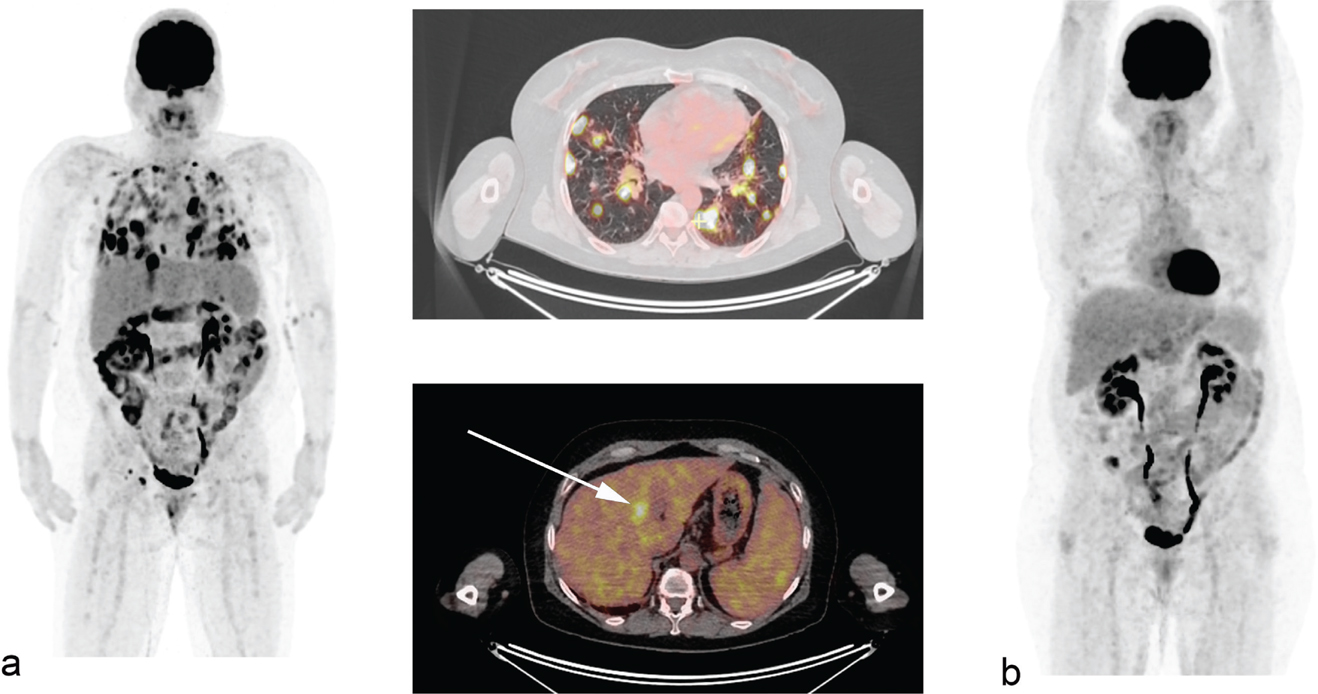

No randomized studies have been performed comparing the outcomes of patients where treatment selections occurred with or without the information provided by PET/CT. In the pre-PET/CT era, bone marrow involvement rate in HL was considered relatively rare compared to rates reported in non-Hodgkin lymphoma. The widespread use of PET/CT has changed this perception and bone marrow involvement represented by focal FDG-avid lesions on PET/CT is observed in around 20% of the patients, a four-fold increase compared to the 5% typically reported when assessing only with bone marrow biopsies (Figure 1). Very few patients will have bone marrow involvement in the setting of a positive bone marrow biopsy and negative PET/CT, and clinically relevant upstaging, as a result of bone marrow involvement by biopsy alone, is exceedingly rare (14, 15). Therefore, the need for invasive staging in HL has been completely abandoned and PET/CT is the only disease staging procedure necessary prior to therapy. The fact that focal FDG-avid bone marrow lesions are reported to be associated with worse outcomes suggest that the additional findings by PET/CT add relevant prognostic information (16, 17). With a first peak in HL incidence around the age of 15–34 years, the large proportion of young patients that are exposed to ionizing radiation is a greater concern than in most other malignancies that occur in older age groups (18). Using a contrast enhanced CT leads to 3 times higher radiation exposure as using a low-dose CT, but using contrast enhanced CT component in PET/CTs rarely changes disease stage or management strategy in lymphoma (1921). Therefore, a contrast-enhanced CT component can be reserved to patients where the added diagnostic value is needed for other medical reasons (7). Another important aspect of contrast-enhanced CT component, in particular in the treatment response assessment setting, is that contrast fluids lead to stronger SUV increase in the liver and mediastinal blood pool as compared to lymphoma tissue (22). As the visual liver to lesion FDG uptake ratio is now the standard way of assessing metabolic response in tumors, this change may have important clinical consequences.

Fig 1

Figure 1. An HL patient with focal lesions in the bone marrow that are not visible of CT. This is one of the most frequent reasons for PET-ascertained upstaging to stage IV disease.